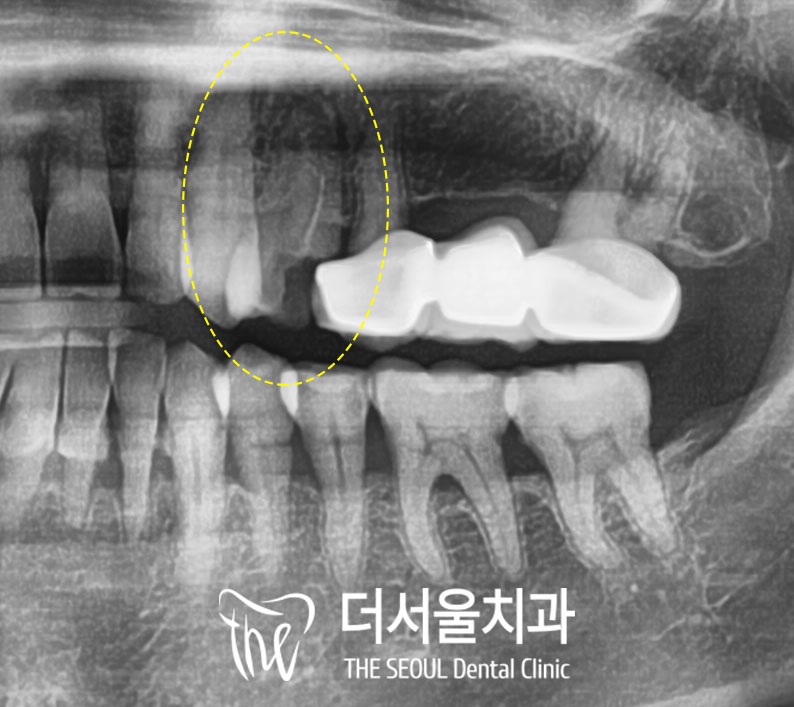

성남치과 에서 촬영한

파노라마 엑스레이를 보면

왼쪽 위 첫 번째 작은 어금니(#24)가

주변 이들보다 작고

거친 형태인 게 보이시죠?

치관이 깨지면서 방사선 투과량이

증가하면 이렇게 보입니다.